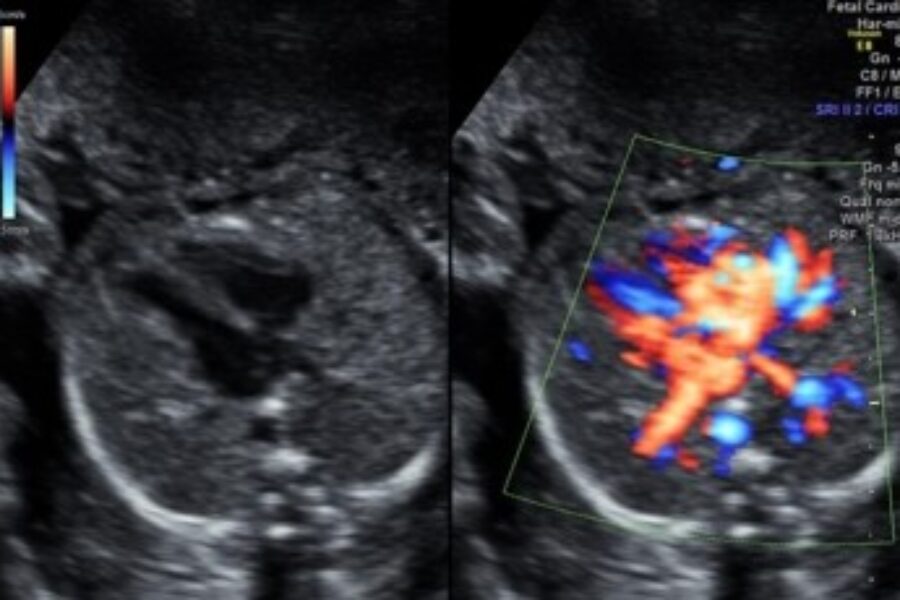

Leeds Congenital Hearts – Fetal

The fetal cardiology Service at Leeds Children's Hospital provides services for pregnant women who require specialist heart scans and investigations.